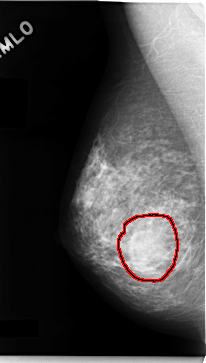

ics_version 1.0 filename C-0060-1 DATE_OF_STUDY 11 3 1993 PATIENT_AGE 47 FILM FILM_TYPE REGULAR DENSITY 3 DATE_DIGITIZED 23 10 1997 DIGITIZER LUMISYS LASER SEQUENCE LEFT_CC LINES 4704 PIXELS_PER_LINE 2624 BITS_PER_PIXEL 12 RESOLUTION 50 OVERLAY LEFT_MLO LINES 4704 PIXELS_PER_LINE 2512 BITS_PER_PIXEL 12 RESOLUTION 50 OVERLAY RIGHT_CC LINES 4704 PIXELS_PER_LINE 2696 BITS_PER_PIXEL 12 RESOLUTION 50 OVERLAY RIGHT_MLO LINES 4712 PIXELS_PER_LINE 2672 BITS_PER_PIXEL 12 RESOLUTION 50 OVERLAY |

FILE: C_0060_1.RIGHT_MLO.OVERLAY TOTAL_ABNORMALITIES 1 ABNORMALITY 1 LESION_TYPE MASS SHAPE ROUND MARGINS CIRCUMSCRIBED ASSESSMENT 3 SUBTLETY 5 PATHOLOGY BENIGN TOTAL_OUTLINES 1 BOUNDARY |